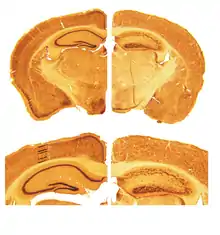

Reeler — мышь-мутант, в организме которой не вырабатывается белок рилин. Наследование мутации имеет аутосомно-рецессивный характер. Отсутствие рилина приводит к нарушению миграции нейронов и дезорганизации слоев коры мозга. У мыши reeler слои коры мозга практически инвертированы, выстраиваясь «снаружи внутрь». Гипоплазия мозжечка приводит к пошатывающейся походке, благодаря которой мышь получила своё название. В субвентрикулярной и субгранулярной зонах мозга у мыши reeler нарушена миграция нейробластов. Исследование мышей reeler позволяет изучить механизмы нейрогенеза и построения мозга и нарушения этих процессов.